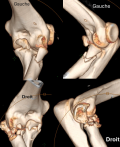

Démarche diagnostique: les radiographies standards ont montré une luxation postéro-externe bilatérale associée aux fractures de la tête radiale et du processus coronoïde (Figure 1). Le patient a été conduit au bloc opératoire en urgence pour une réduction orthopédique sous sédation. Après réduction, des attelles brachio-antébrachio-palmaires bilatérales ont été mises en place en position fonctionnelle, en attendant la prise en charge chirurgicale définitive. Un scanner reconstruction 3D bilatéral des coudes a été réalisé en post-réduction afin de mieux évaluer (Figure 2). La morphologie des fractures de la tête radiale, la taille et la localisation du fragment du processus coronoïde, l'état des surfaces articulaires et des structures associées. Cette imagerie nous a permis de planifier la stratégie chirurgicale adaptée pour chaque coude, notamment en termes de fixation interne et de traitement des fractures de la tête radiale et du processus coronoïde.

L'examen scannographique du coude droit met en évidence une fracture comminutive de la tête radiale, correspondant à un Mason type III selon la classification modifiée de Hotchkiss. Une fracture associée de l'apophyse coronoïde droit est observée, classée type II selon Regan et Morrey. Du côté gauche, le scanner montre une fracture moins sévère de la tête radiale, correspondant à un Mason type II intéressant le col du radius, ainsi qu'une fracture discrète de l'apophyse coronoïde, type I selon Regan et Morrey.

Figure 2: scanner du coude droit et gauche montrant les fractures de la tête radiale et du processus coronoïde après réduction des luxations